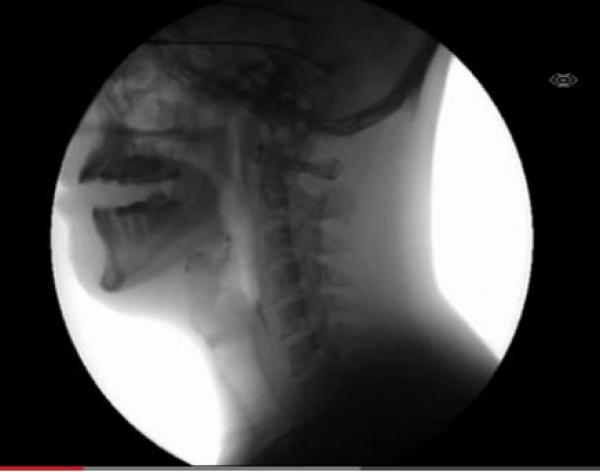

قال تعالى "لقد خلقنا الإنسان في أحسن تقويم" ..نشاهد في هذا المقطع المصور بتقنية أشعة إكس " X Ray".. دخول الطعام الى فم الانسان ثم البلعوم ثم الى المعدة.

وتتجلى في الفيديو عظمة الخالق سبحانه وتعالى حينما يدخل الطعام الى فم الإنسان ، حيث تقوم اللهاه بغلق مجرى التنفس تجنا لدخول أي طعام الى الرئتين ومن ثم يدخل الطعام الى البلعوم ثم المرئ ومن ثم الى المعدة ..فتبارك الله الخالق المصور..